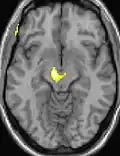

| Diese Kernspintomographie mit eingezeichneter Morphometrie zeigt einen höheren Anteil an Grauer Substanz im Hypothalamus rechts (im Bild links) | ||

Die Positronen-Emissions-Tomographie (PET)-Darstellungen oben zeigen die funktionellen Daten, also die Bereiche, welche bei Schmerzen Aktivität aufweisen, im Vergleich zum Aussehen bei einem schmerzfreien Intervall. Man sieht die sog. Schmerzmatrix, die immer bei Schmerz aktiviert ist und das Areal in der Mitte (in allen drei Ebenen), welches spezifisch im Cluster-Kopfschmerz aktiviert ist. Die VBM Bilder unten zeigen die strukturellen Daten. Hier wird untersucht, ob die Gehirne von Cluster-Kopfschmerz-Patienten anders sind als die Gehirne von Menschen ohne Kopfschmerzen. Nur ein Areal ist anders, da es mehr Graue Substanz enthält: Dieses entspricht dem oben gezeigten funktionellen Areal. Es handelt sich um den Hypothalamus. Dort wird unter anderem der Schlaf-Wach-Rhythmus generiert. Man vermutet daher den Motor des Cluster-Kopfschmerzes im Hypothalamus.[27][28] Mit der 1H-Magnetresonanzspektroskopie konnten auch biochemische Unterschiede zwischen dem Hypothalamus gesunder Menschen und dem Hypothalamus von Cluster-Kopfschmerz-Patienten nachgewiesen werden.[29][30]